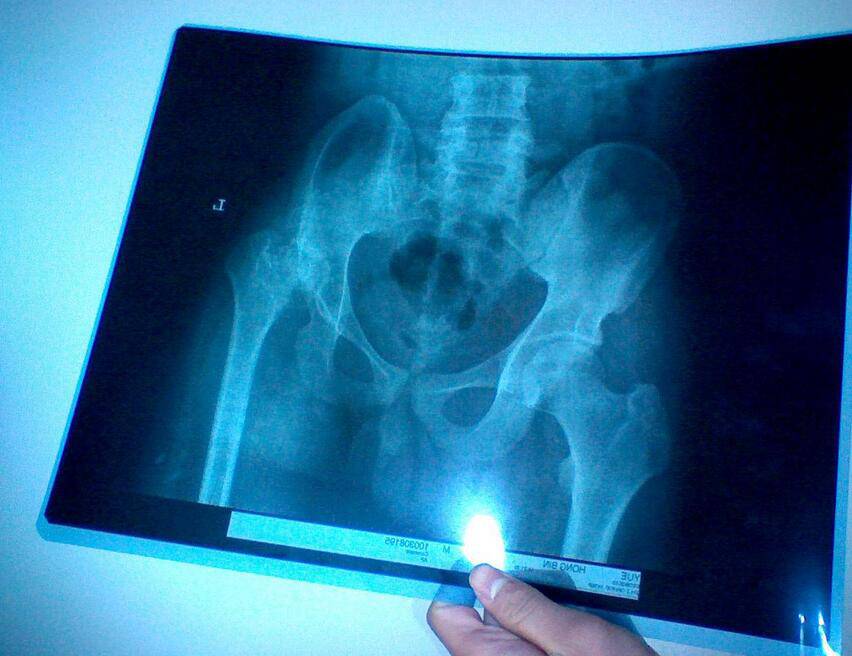

股骨頭壞死四大常見(jiàn)癥狀 9款食療助康復(fù)

股骨頭壞死的臨床表現(xiàn)